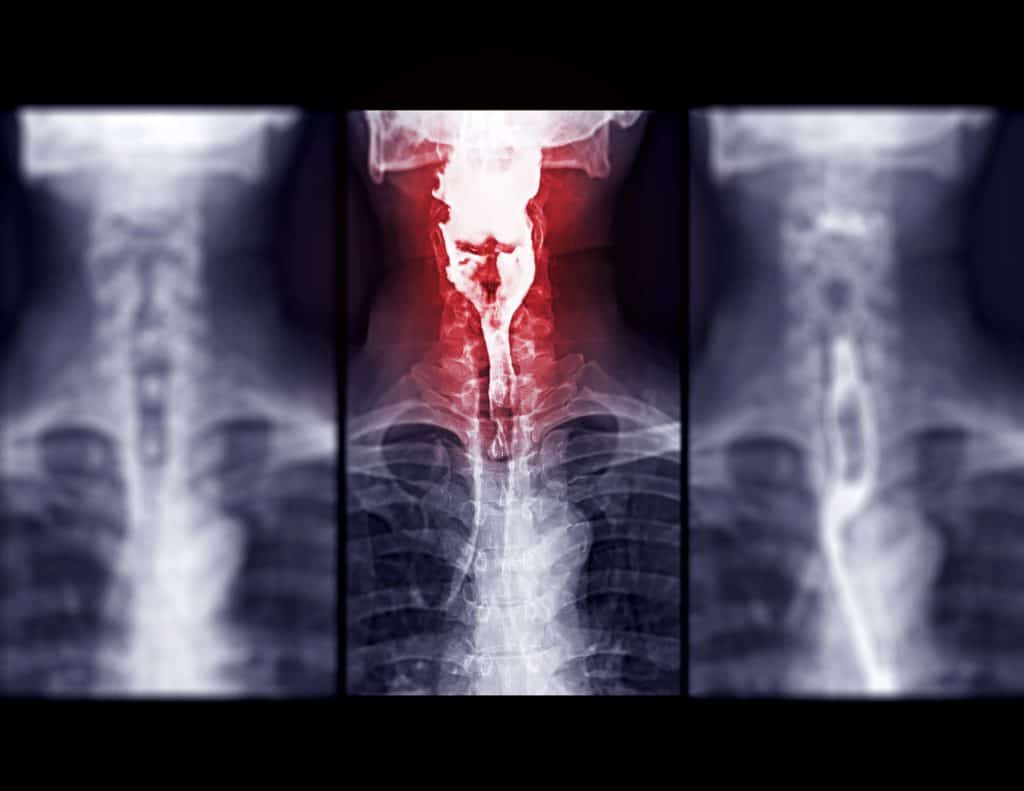

Dijagnoza bolesti Barrettov jednjak postavlja se prije svega dobivanjem informacija o simptomima bolesne osobe. Po potrebi liječnik specijalist će odrediti i drugi detaljan pregled. U slučaju pojave komplikacija bolesti primjenjuje se i radikalno, kirurško liječenje. S ciljem prevencije preporučuju se rutinske endoskopije kod svih osoba starijih od 40 godina. Važno je definirati simptome koji upućuju na Barrettov jednjak, liječnik će utvrditi što pacijentu najviše smeta, važno je da li netko iz obitelji pacijenta ima istu dijagnozu. Potrebne su također laboratorijske dijagnostičke metode, testovi krvi, urina, proučavanje fecesa, ispitivanje razine kiselosti u želucu provođenje ezofagogastroduodenoskopije (ispitivanje unutarnje površine gastrointestinalnog trakta). Liječnik određuje ako je potrebno napraviti biopsiju kako bi utvrdio strukturu organa i odredio oštećenje sluznice. Rendgenski pregled probavnog trakta i manometrija (proučavanje probavnog trakta) se isto rade, kao i respiratorna dijagnoza te ultrazvučni pregled. Nakon opsežne dijagnostike liječnik određuje da li je prikladno kirurško liječenje ili endoskopija, laserski tretman ili drugi oblik terapije.